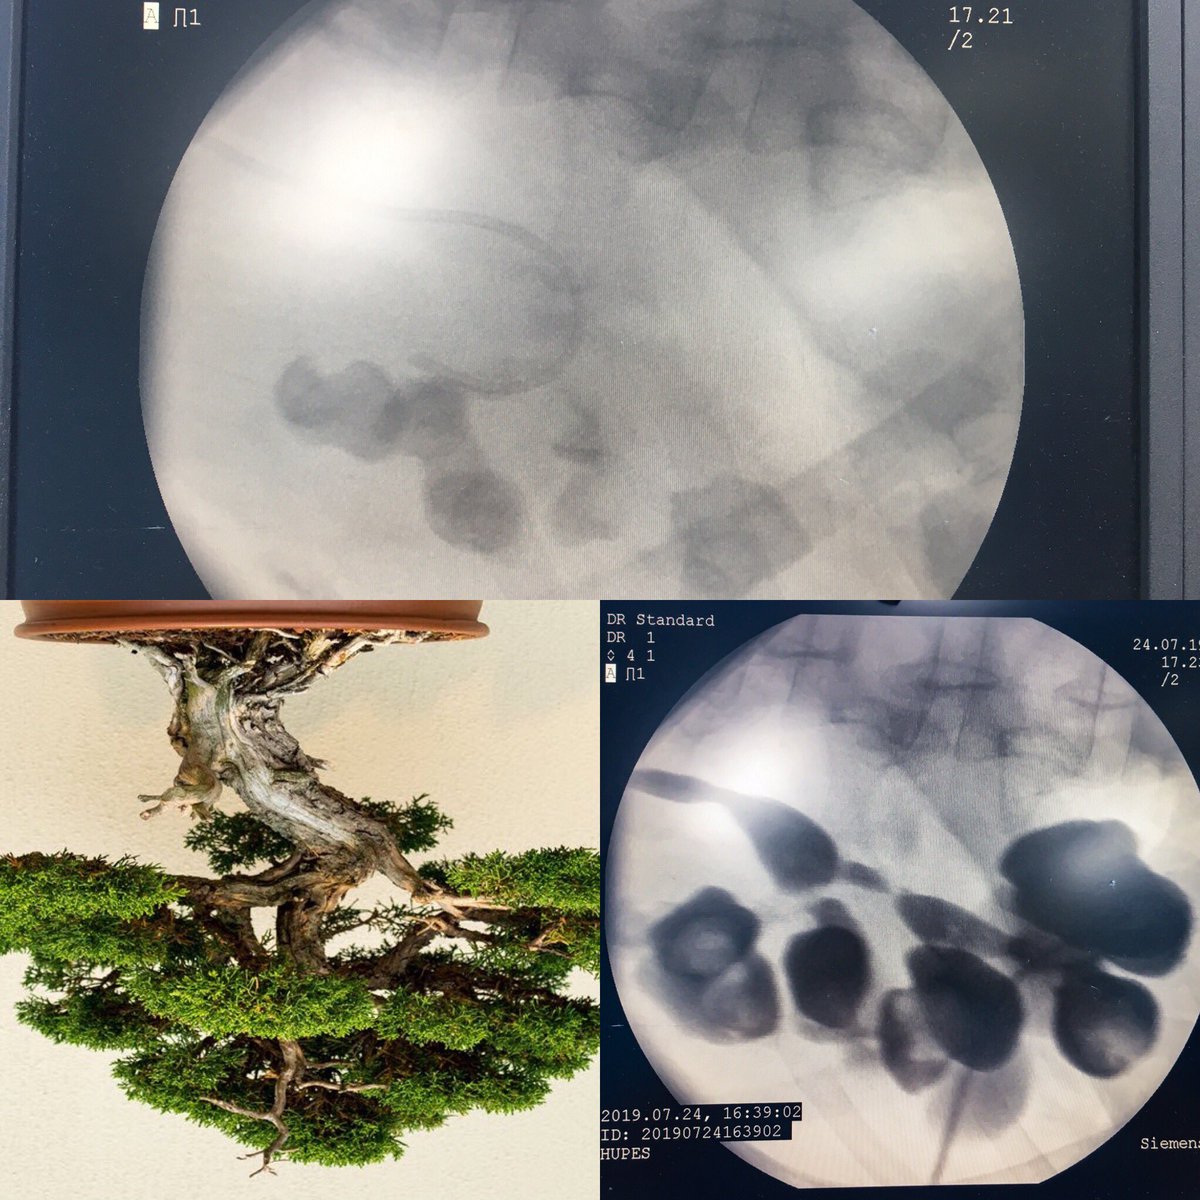

PCNL challenges

Eduardo Cruz-Nuricumbo MD Professor endourology